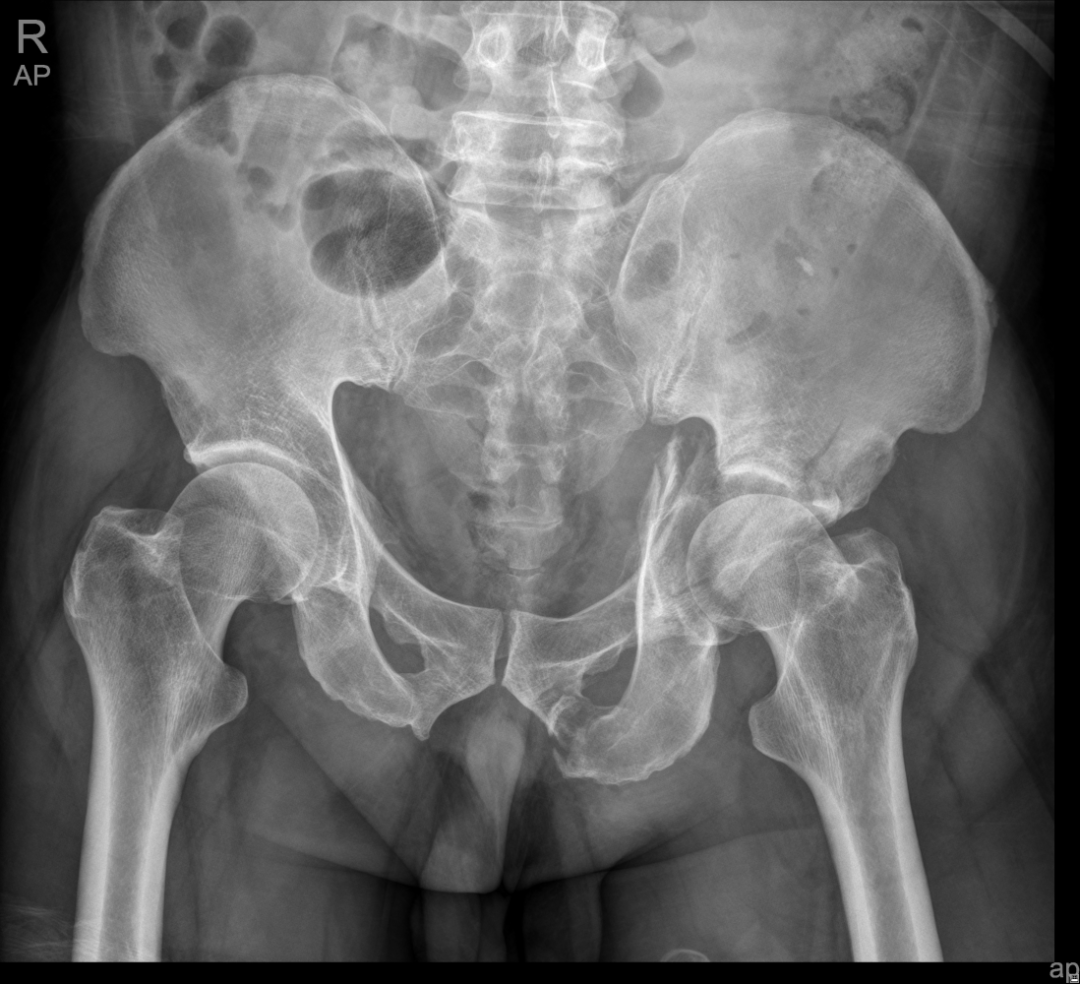

The acetabular fracture, known as “the Pearl of the Crown” of traumatic orthopedics, is the most difficult problem to handle. Only when the surgery is done meticulously, can targeted treatment be achieved. Therefore, if doctors in a hospital are capable to perform such a complex surgery for treating acetabular fracture, it reflects that the hospital’s medical level in trauma emergency and orthopedics is relatively high.

In April this year, the Traumatic Orthopedics Center of the Shenzhen Second People’s Hospital performed its first internal fixation surgery by combining the pararectus approach with K-L approach for acetabular fracture. This surgical technique is a new anterior surgical approach that is popular at home and abroad in recent years. It can guarantee the acetabulum could be exposed directly through the incision and is less invasive than the ilioinguinal approach. However, the incision is so close to the external iliac artery and the femoral nerve that it requires the surgeon to be familiar with the anatomical position and to have a high level of surgical technique. The pararectus approach is the most popular approach widely used for acetabular fractures surgery due to its advantages of less invasive and more targeted.

A hip fracture is a super serious injury, which is typically the result of a high-energy event. It can be caused by the surrounding fractures of the pubis, ischium or ilium, or by a central dislocation of the hip. Clinical symptoms of a hip fracture include local pain, swelling and bruising in and around the hip areas, for example, around the pudendum, groin or lumbar, and inability to get up from a fall or to walk, and shorter leg on the side your injured hip.

The clinical and research focuses of the center are on digital orthopedics, treatment of periarticular fractures and nonunion, deformity correction, and functional limb reconstruction. The center mainly treats various types of limb fractures, severe open injuries with neurovascular injuries, acetabular fractures, massive soft tissue defects, chronic osteomyelitis and infected nonunion, limb deformities, limb dysfunction, etc. And its clinical and scientific research capacity in the following areas has reached advanced national level, which are the application of minimally invasive techniques and orthopedic robotic navigation and positioning system on internal fixation surgery for fractures, the application of digital orthopedic techniques in the treatment of periarticular fractures, bone transport techniques for the treatment of infected bone nonunion, and functional limb reconstruction.